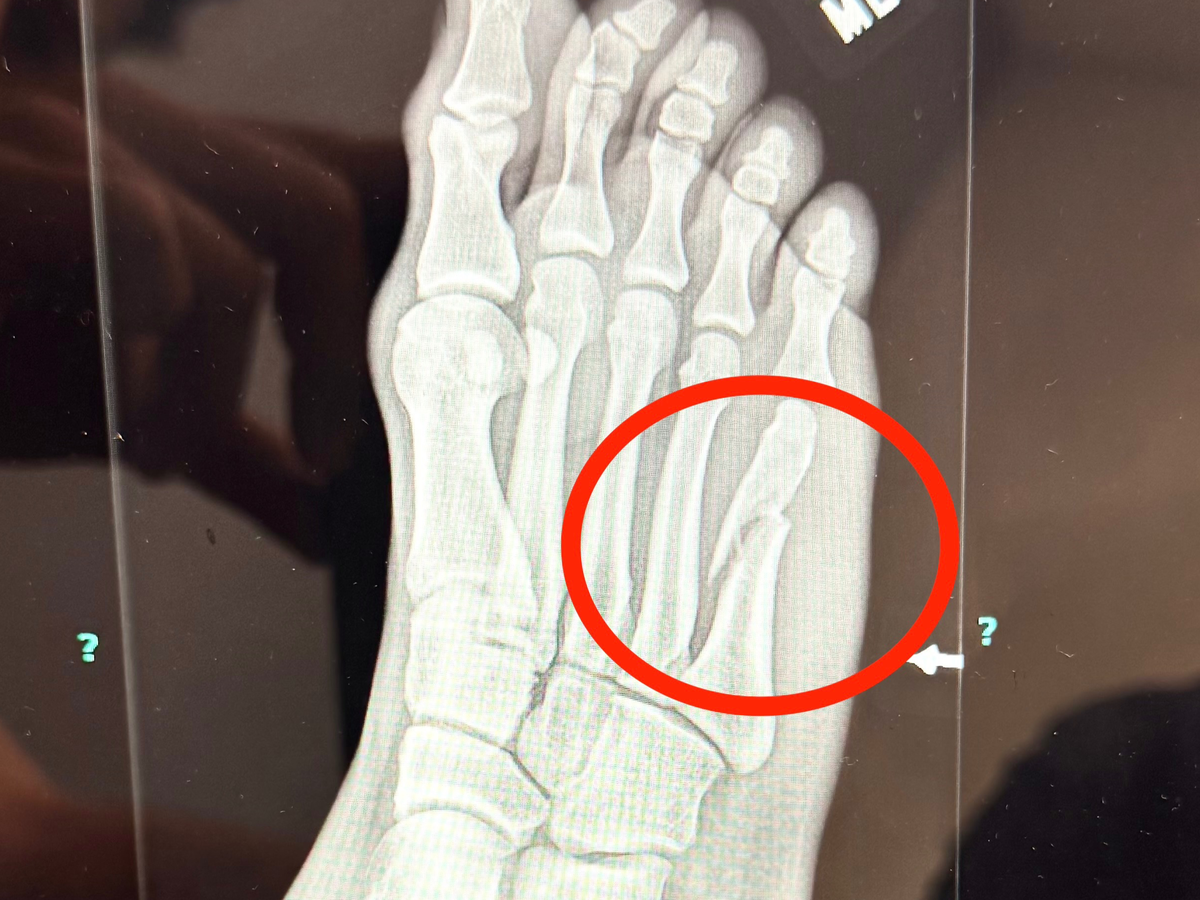

In mid October, during an audition for Romeo and Juliet, I landing awkwardly in petite allegro (doing a pas de bourée, of all steps...) and completely snapped my fifth metatarsal! My orthopedic surgeon is recommending I get surgery, as it will be the most effective treatment with the quickest recovery. If all goes well, I am hoping to be back to dancing by late January!